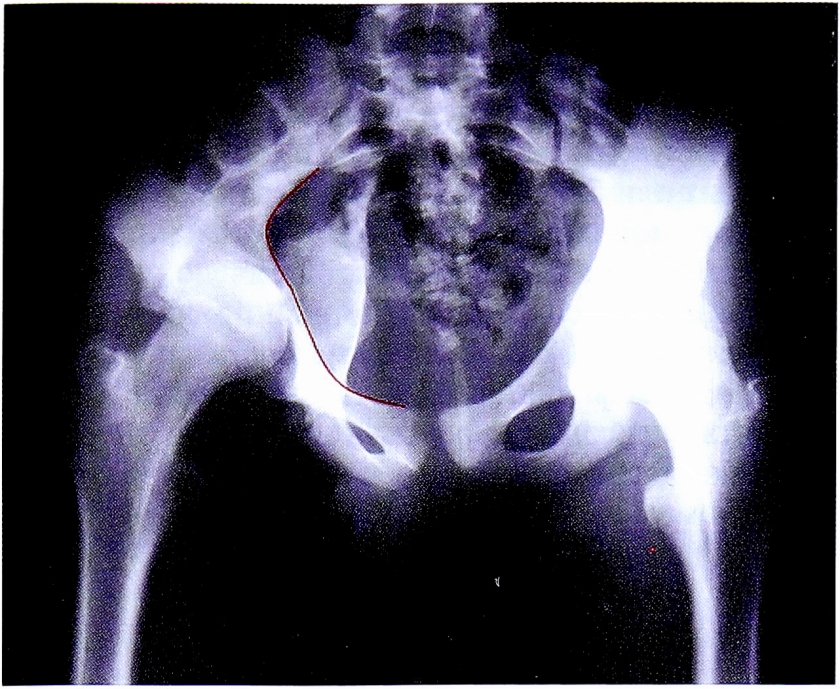

Как уже было отмечено в первом клиническом примере, при сохранении непрерывности подвздошно-гребешковой линии на обзорной рентгенограмме, можно исключить переломы передней колонны, как простые, так и ассоциированные с переломами других отделов (рис. 26).

Рис. 26. Первый этап определения перелома задней колонны.

Fig. 26. First step of posterior column fracture diagnostic.

Следует отметить, что в данном примере (рис. 27) имеется повреждение линии заднего края, что соответствует повреждению задних отделов впадины. Однако повреждение этой линии в одном месте и, соответственно, отсутствие отдельного фрагмента задней стенки позволяет с большой долей вероятности исключить те типы переломов, при которых он наблюдается, а именно: перелом задней стенки и перелом задней колонны, ассоциированный с переломом задней стенки.

Рис. 27. Второй этап определения перелома задней колонны.

Fig. 27. Second step of posterior column fracture diagnostic.

Таким образом, методом исключения неповрежденных структур вертлужной впадины, диагностирован перелом задней колонны вертлужной впадины. Повреждение подвздошно-седалищной линии и деформация контуров запирательного отверстия подтверждает этот диагноз (рис. 28). На рентгенограмме в косой запирательной проекции определяется задний вывих головки бедренной кости и отсутствие отдельного фрагмента задней стенки (рис. 29).

Рис. 28. Верификация перелома задней колонны.

Fig. 28. Verification of posterior column fracture.

Рис. 29. Рентгенограмма в косой запирательной проекции.

Fig. 29. Obturetor oblique view.